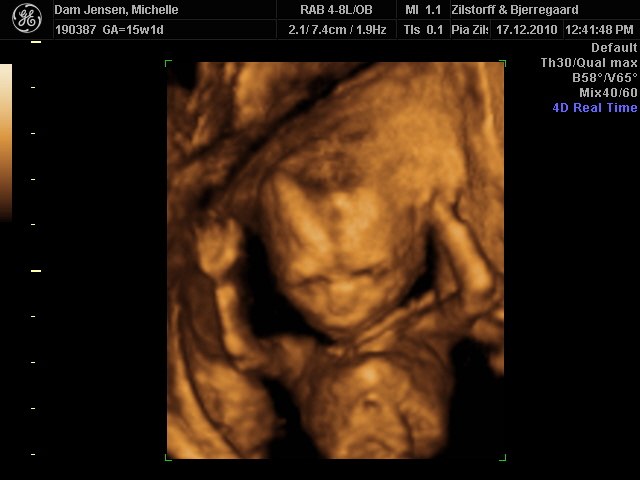

Det var så fantastisk at se hende i 3D selvom jeg ikke var længere henne end 15+1

men vægt mæssigt er hun 15+3 hehe så hun spiser godt må man sige

Alt var perfekt, hjerter, nyre, kranie tarme osv.. så vi var super stolte og glade